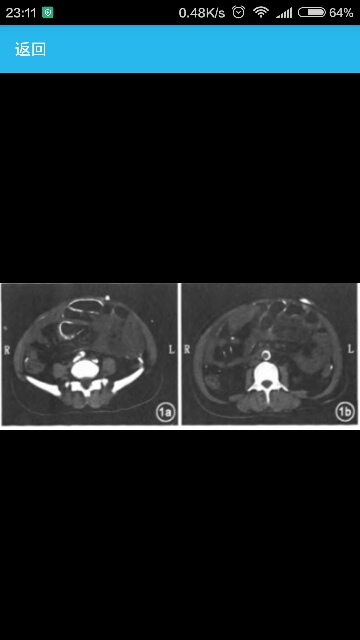

女性,因“维持性腹膜透析7年余,腹痛、腹胀5d”就诊 体温36.5℃,脉搏105次/min,呼吸20次/min,血压165/94 mmHg(1mm Hg=0.133 kPa),慢性病容,贫血貌,表情痛苦。双肺呼吸音清,未闻及于湿罗音。心界向左下扩大,未闻及瓣膜区杂音。腹部膨隆,叩诊呈鼓音,右侧腹部可见腹膜透析管引出,出口处周围皮肤不红,未见分泌物,全腹软,压痛及反跳痛明显,未触及包块,肠鸣音亢进,10次/min,双下肢轻度水肿。 病史患者1994年诊断为“慢性肾功能不全(尿毒症期)”,并开始规律腹膜透析治疗(2.5%腹膜透析液2L,3次/d。1.5%腹膜透析液2L,1次/d),每天超滤量约1000ml。 入院前1个月出现腹痛、腹胀、腹膜透析液浑浊,诊断“腹膜透析相关性腹膜炎”,抗感染治疗后症状缓解,入院前5天出现恶心呕吐、腹胀,至入院时未解大便。 临床表现 辅助检查Hb 109g/L,白细胞9.67×109/L,中性粒细胞比例0.843,白蛋白23.4 g/L,肌酐492 μmol/L,钙1.97 mmol/L,磷1.25 mmo/L,甲状旁腺素136.9 pmol/L,腹膜透析液培养出G+菌和近平滑念珠菌。 腹部B超:腹腔积气、积液。双肾缩小伴多发囊肿。 腹部CT:腹膜、大网膜、肠系膜及腹盆腔内肠管壁广泛增厚肿胀,伴广泛钙化,肠管僵硬,管腔积液、积气,多发小气液平。网膜囊及腹腔内少量积液,部分局限,盆腔间置管影。双肾萎缩伴多发囊性低密度灶,多系囊肿;双侧肾盂肾盏多发结石。双侧桥隔及肾筋膜增厚。 颈部CT:双侧甲状旁腺增大,右侧可见钙化点。双侧颈内动脉壁、颈总动脉起始部及分又部、主动脉弓壁钙化。 诊断包裹性腹膜硬化 治疗给予禁食、胃肠减压、肠道外营养、茴香热敷腹部、抗真菌及细菌等治疗,并行腹膜透析置管拔除术,血液透析。治疗5d后,患者症状缓解,开始进食,大便恢复。